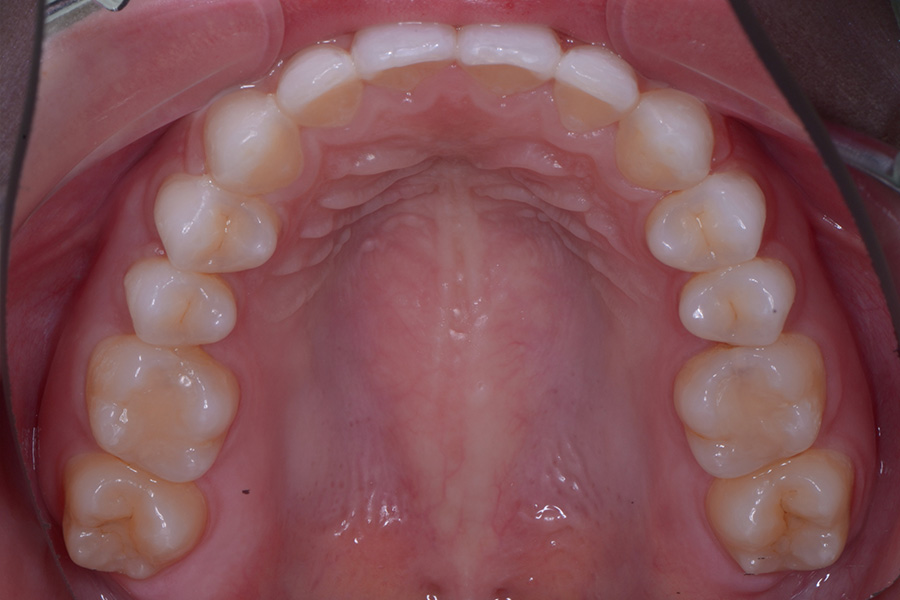

【20代女性】

前歯のすきっ歯と

捻じれを治したい

治療後

主訴 前歯のすきっ歯と捻じれを治したい

期間 8か月

費用 40万円(別途調整料)

治療内容 上下顎ラビアル矯正(表側矯正)